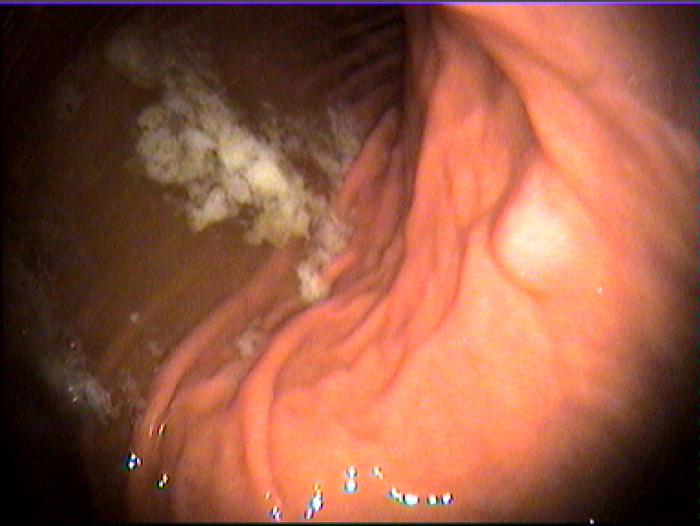

福州台江医院胃病诊疗科室医师指出,萎缩性胃炎是指胃黏膜表面反复受到损害后导致的黏膜固有腺体萎缩,甚至消失,黏膜肌层常见增厚的病理改变。